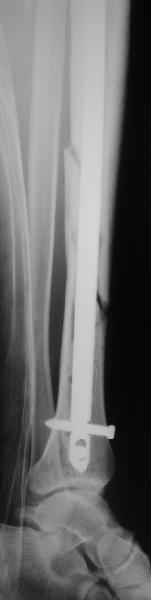

КА> Но почему решение динамизировать на сроке 8 недель с полным

В приложении картинка пациента со сломанным внизу гвоздем. Начал лечение в другом учреждении. Еще и адвокат к тому же.

Динамизировали через 8 недель, а оно поползло больше, чем хотелось бы.

В Кемпбелле можно прочитать, что Fractures in the distal third of the tibia had the highest frequency of nail breakage.

Вообще, этот вопрос обсуждался давно, и еще в статье R. Bucholz (1987) про переломы гвоздей указывалось, что расстояние от ближайшего отверстия до перелома должно быть не менее 5 см, иначе есть угроза усталостного перелома. По литературе переломы гвоздей в нижней трети

tibia достигают 4,3%.